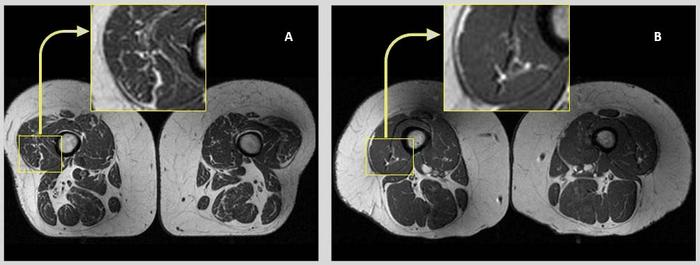

Axial T1-weighted bilateral thigh MR images and magnified frames providing a closer look at the areas in lateral aspects of quadriceps femoris muscles (knee extensors) from two obese, female participants, aged 58 (A) and 62 years (B), respectively. In A, the thigh muscles on both sides demonstrate abundant fatty streaks, consistent with a high Goutallier grade of 45 for this participant, whose diet from the past 12 months consisted 68% of ultra-processed foods. In B, the thigh muscles show fewer fatty streaks as highlighted in the magnified image, consistent with a low Goutallier grade of 17 for this participant, whose diet contained only 36% ultra-processed foods.

“Research from our group and others has previously shown that quantitative and functional decline in thigh muscles is potentially associated with onset and progression of knee osteoarthritis,” Dr. Akkaya said. “On MRI images, this decline can be seen as fatty degeneration of the muscle, where streaks of fat replace muscle fibers.”